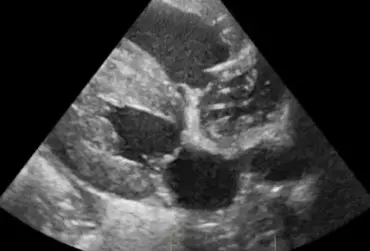

Określenie „rozpoznanie cioci Minnie” pochodzi ze Stanów Zjednoczonych i jest żartobliwym określeniem rozpoznania patognomonicznego, stosowanym głównie przez radiologów. Zwrot ten stał się popularny w latach 90. XX w. za sprawą strony internetowej o takim tytule. Obecnie to określenie stosuje się również w metodologii nauczania klinicznego. W artykule przedstawiono przypadki rozpoznań „cioci Minnie” z własnego archiwum ultrasonografii jamy brzusznej małych zwierząt.